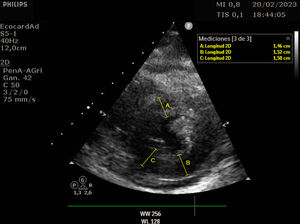

Se trata de una mujer de 41 años con deficiencia humoral y gammapatía monoclonal IgG lambda, que acude al servicio de Urgencias con fiebre y debilidad, siendo diagnosticada de infección respiratoria secundaria a Influenzae A. Veinticuatro horas después ingresa en el servicio de Medicina Intensiva por hipotensión severa, con necesidad de noradrenalina hasta 0,5 ug/kg/min, hipoalbuminemia y hemoconcentración. Se estableció el diagnóstico de síndrome de fuga capilar sistémica con edema intramiocárdico. El síndrome de fuga capilar sistémica es una condición caracterizada por la fuga de plasma y proteínas al compartimento intersticial, y se asocia con gammapatía monoclonal y frecuentemente aparece después de una infección del tracto respiratorio superior, siendo el edema intramiocárdico una complicación poco frecuente. En nuestra paciente, se realizó un ecocardiograma transtorácico al ingreso, mostrando una función ventricular sistólica dentro del límite inferior de la normalidad (FEVI 50-55%), con comportamiento restrictivo, además se evidencia un engrosamiento difuso del miocardio: eje largo paraesternal (fig. 1 y vídeo A), eje corto paraesternal a nivel apical (fig. 2), y plano apical cuatro cámaras (fig. 3), probablemente secundario a edema intramiocárdico, ya que un ecocardiograma transtorácico realizado 1 mes antes mostró grosores normales, eje largo paraesternal (fig. 4). Se prescribió tratamiento con inmunoglobulinas y corticosteroides, pero lamentablemente la paciente falleció 24 horas después del ingreso debido a un shock refractario.